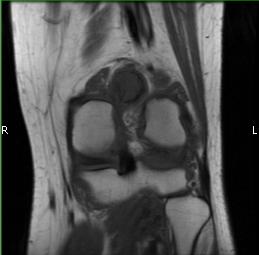

MRI (Fig. 1-10)

- Periarticular or synovial nodular mass with varying degrees of bone erosion.

- Nodular lesion with areas of hemosiderin (low signal on all sequences) and hemorrhage.

- On fat suppress images the tumor is high signal and hemosiderine cannot be seen.

- Joint effusions and bony erosions are well demonstrated. As with CT, contrast enhancement is typical.

Fig. 1-10: Magnetic Resonance of a PVNS of the knee shows a synovial mass with minimal bone erosion of the medial articular plate. On T1W and T2W images shows a tumor with low intensity areas (hemosiderin) and hemorrhage. Joint effusion is well demonstrated. Post contrast images demonstrate an irregular pattern of enhancement.